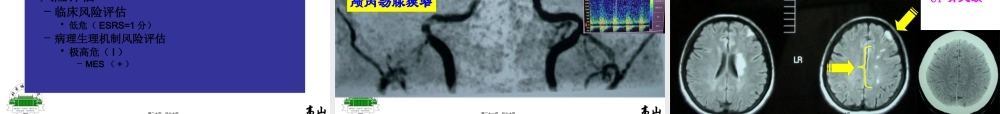

分层治疗病例分析大动脉粥样硬化性缺血性卒中高山北京协和医院神经内科第一页,共六十页。高山大动脉粥样硬化心源性卒中穿支动脉疾病缺血性卒中病因分型其他原因烟雾病夹层动脉瘤动脉炎等第二页,共六十页。高山粥样斑块、血小板聚集血小板(+++)血脂(+++)大动脉粥样硬化性50%↑需强化抗血小板和强化他汀治疗病人LiuHM,etal.Stroke1996;27:650–3.HuangYNetal.Neurology1997;48:524–5.WongKS.Stroke2000;31:2641–7第三页,共六十页。高山脑卒中/TIA二级预防中他汀药物的分层用药其它缺血性卒中或TIA(除外心源性)缺血性卒中或TIA,伴以下任一危险因素:•颅内外动脉粥样硬化•糖尿病•冠心病•代谢综合征•持续吸烟缺血性卒中或TIA,属于以下任一种情况:•有动脉-动脉栓塞证据•有脑动脉粥样硬化易损斑块证据临床描述强化降脂>2.1mmol/L(80mg/dl)极高危(II)强化降脂立即启动标准降脂>2.6mmol/L(100mg/dl)高危LDL-C目标值他汀治疗方案启动他汀的LDL-C危险分层极高危(I)极高危(II)高危<2.6mmol/L(100mg/dl)或降低幅度30-40%<2.1mmol/L(80mg/dl)或降低幅度>40%他汀类药物防治缺血性卒中/短暂性脑缺血发作专家共识组.中华内科杂志;2008;47:873-875第四页,共六十页。高山氯吡格雷75mg/d或阿司匹林75-150mg/d其它非心源性缺血性卒中或TIA缺血性卒中或TIA,1、动脉粥样硬化性2、伴有重要危险因素(既往卒中史、糖尿病、冠心病、外周血管病)缺血性卒中/TIA,伴1、脑动脉支架或其他成形术2、不稳定性心绞痛3、无Q波心梗临床描述氯吡格雷75mg/d+阿司匹林75-150mg/d治疗方案危险分层极高危高危中度高危阿司匹林75-150mg/d或氯吡格雷75mg/d脑卒中/TIA预防中抗血小板治疗的分层用药(根据共识)第五页,共六十页。高山氯吡格雷75mg/d或阿司匹林75-150mg/d其它非心源性缺血性卒中或TIA缺血性卒中或TIA,1、动脉粥样硬化性2、伴有重要危险因素(既往卒中史、糖尿病、冠心病、外周血管病)缺血性卒中/TIA,伴1、脑动脉支架或其他成形术2、不稳定性心绞痛或无Q波心梗3、动脉到动脉栓塞临床描述氯吡格雷75mg/d+阿司匹林75-150mg/d治疗方案危险分层极高危高危中度高危阿司匹林75-150mg/d或氯吡格雷75mg/d脑卒中/TIA预防中抗血小板治疗的分层用药(共识+个人观点)第六页,共六十页。高山颈内动脉系统极高危病例-1•男,74岁•就诊当天早晨出现发作性言语不清,持续2-3分钟•后反复出现答非所问,右侧肢体无力,持续10-15钟•至下午4点共发生5次•急...